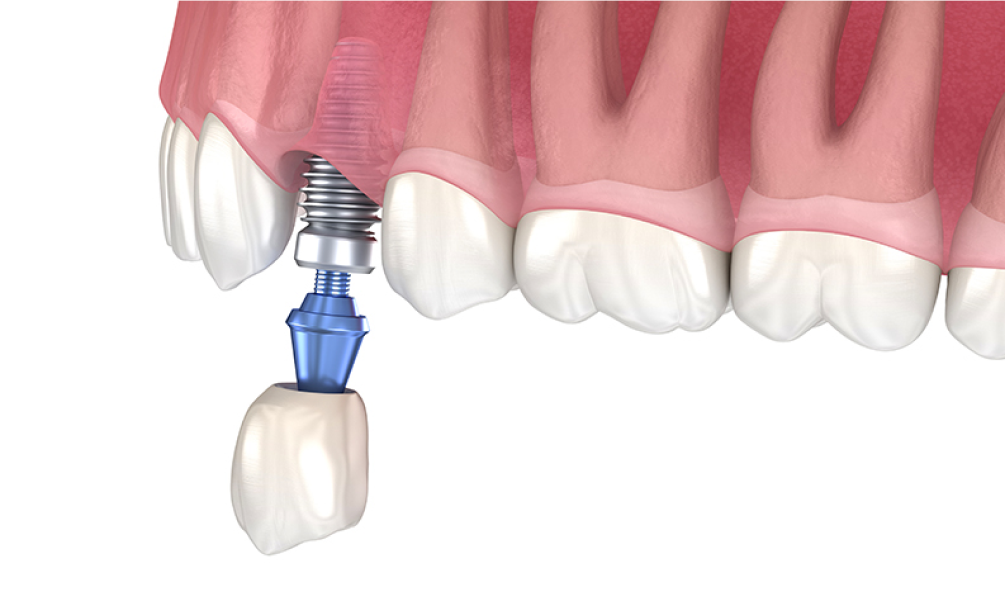

• 임플란트 치근 식립

STEP 03 임플란트 치근 식립

잇몸뼈가 완전히 융합하여 자리 잡은 것을 확인한 뒤 임플란트의 인공치근을 식립합니다.

• 보철물 결합

STEP 04 보철물 결합, 수술 완료

임플란트의 인공치근이 단단하게 고정된 후에 환자에게 맞춤 제작한 보철물을 상부에 결합시켜 수술이 완료됩니다.